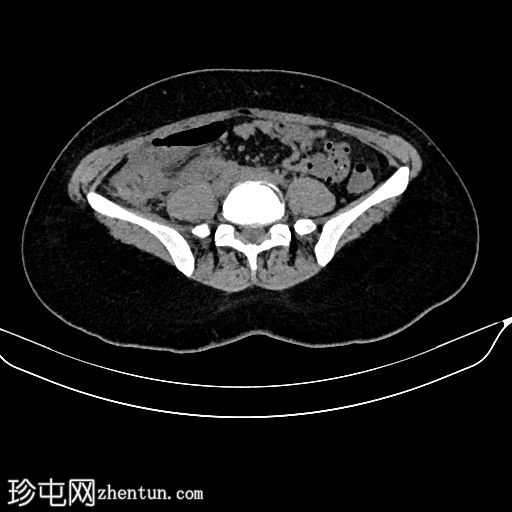

平扫

3.jpg

右肾周间隙可见高密度影(HU=65),经右侧结肠旁沟延伸至肾盂。

右肾上极区可见一较大、边界清晰、以脂肪密度为主、伴有实性强化成分的病灶,延伸至肾盂。

该病灶延伸至肾盂区域并推移肾盏;但未见侵犯或肾积水。

符合血管平滑肌脂肪瘤破裂的特征。